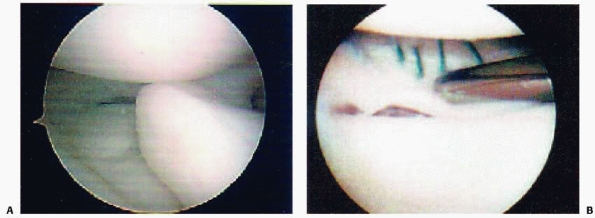

series of 80 skeletally immature patients who underwent surgical

fixation of tibial eminence fractures, Kocher et al.177 found no associated chondral injuries and associated meniscal tear in only 3.8% (3/80) of patients (Fig. 24-1). Associated collateral ligament injury

or proximal ACL avulsion are uncommon, but have been reported.131,252

displaced tibial eminence fragment has been reported and may be a

rationale for considering arthroscopic or open reduction in displaced

tibial spine fractures (Fig. 24-5).54,59,94,177

Meniscal entrapment prevents anatomic reduction of the tibial spine

fragment, which may result in increased anterior laxity or a block to

extension.120,148,211,236,240 Furthermore, meniscal entrapment itself may cause knee pain after fracture healing.59 Falstie-Jensen and Sondergard Petersen,94 Burstein and colleagues,54 and Chandler and Miller59

have all reported cases of meniscal incarceration blocking reduction of

type 2 or 3 tibial spine fractures in children. The prevalence of

meniscal entrapment in tibial spine fractures may be common for

displaced fractures. As aforementioned, the anterior horn of the

lateral meniscus typically remains attached to the tibial eminence

fracture fragment. However, the anterior horn of the medial meniscus or

the intermeniscal ligament may become incarcerated. Mah and colleagues200

found medial meniscal entrapment preventing reduction in 8 of 10

children with type 3 fractures undergoing arthroscopic management. In a

consecutive series of 80 skeletally immature patients who underwent

surgical fixation of hinged or displaced tibial eminence fractures

which did not reduce in extension, Kocher et al.177

found entrapment of the anterior horn medial meniscus (n = 36),

intermeniscal ligament (n = 6), or anterior horn lateral meniscus (n =

1) in 26% (6/23) of hinged (type 2) fractures and 65% (37/57) of

displaced (type 3) fractures. The entrapped meniscus can typically be

extracted with an arthroscopic probe and retracted with a retaining

suture (Fig. 24-6).